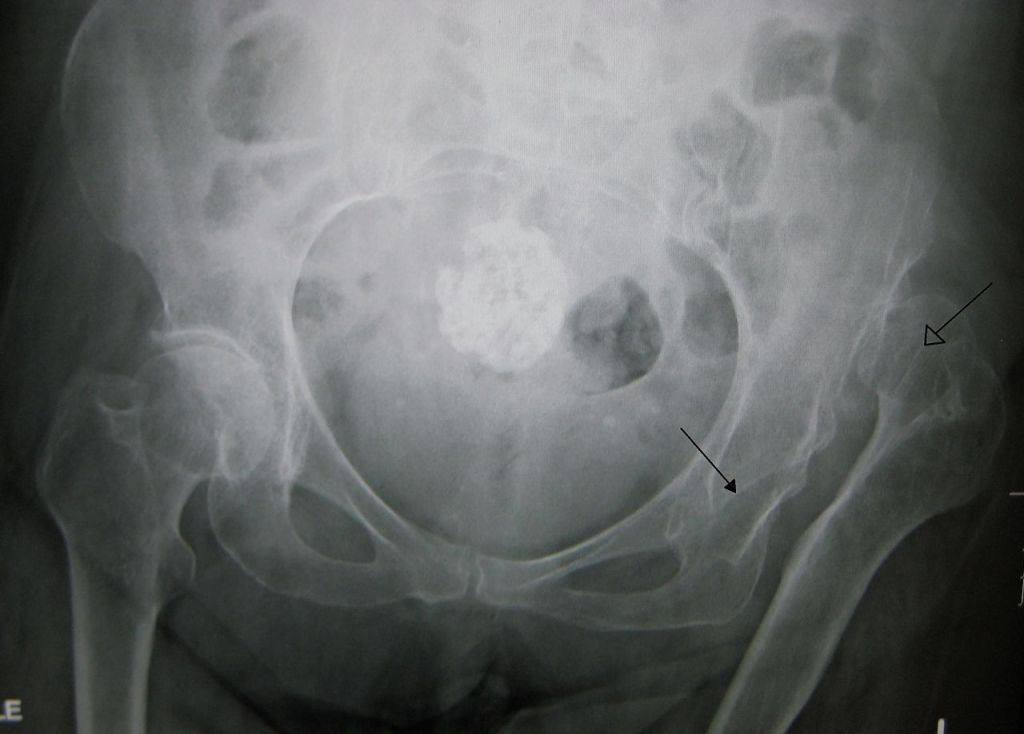

XRAY OF HIP DYSPLAYSIA

Radiographs (X-rays) of an average dog’s pelvis and hips. The head of the femur (arrow) is seated profoundly within the acetabulum, showing remarkable hip joint congruity.

Total hip replacements are usually very successful for the lifetime of your pet, and active dogs are able to resume a can activity for the rest of their lives. Radiographs (X-rays) of a young dog with subluxation of both hip joints after hip dysplasia.

Many pets with hip dysplasia can be succeeded with conservative/medical therapy. Traditional medicine does not cure arthritis caused by hip dysplasia but is aimed at controlling it. Still, it isms to prevent (hip pain, lameness, reluctance to exercise). Conservative treatments include joint administering an ®, Cosequin ®), pain medications, weight loss, and rehabilitation. Many dogs can be made comfortable with conventional treatment; however, arthritis, pain, and lameness often worsen over time. At this point, surgery is usually recommended. Radiographs (X-rays) of a mature dog with degenerative joint disease secondary to chronic hip dysplasia.